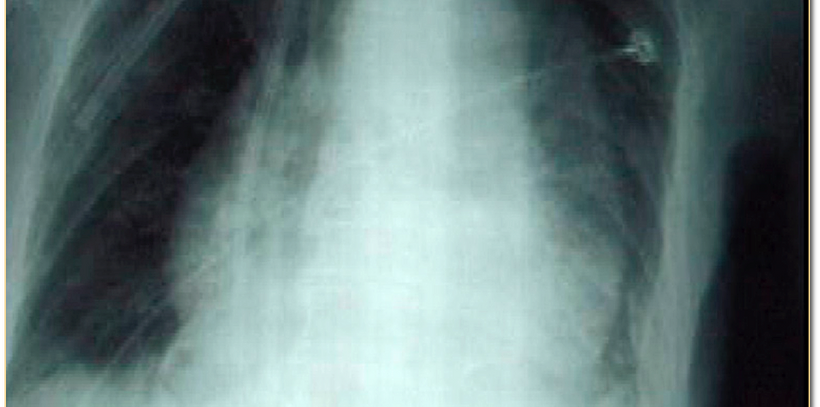

Chest X Ray Thoracic Aortic Aneurysm

Chest X Ray Thoracic Aortic Aneurysm Photos

Photos of Chest X Ray Thoracic Aortic Aneurysm

Chest X Ray Thoracic Aortic Aneurysm Pictures

Images of Chest X Ray Thoracic Aortic Aneurysm

Chest X Ray Thoracic Aortic Aneurysm Images